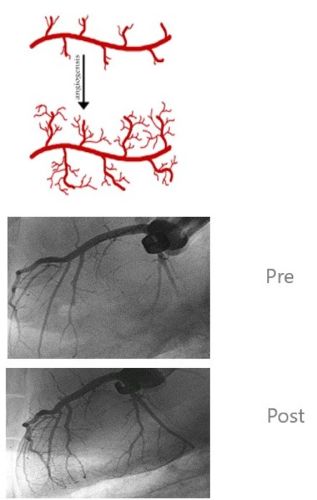

この衝撃波のレベルを低くした、低エネルギー衝撃波には、細胞内で血管形成要素を放出させて、新血管の形成を促進させる作用があることが証明され、この新生血管形成促進効果を利用して、形成外科(美容治療)、狭心症、ED(男性性機能障害)など幅広い分野において応用され、既にさまざまな効果が実証されてきている

衝撃波による血管再生メカニズム

低強度衝撃波の照射

血管が揺さぶられ細胞内外で反応が起こる

血管内皮細胞で一酸化窒素合成酵素(eNOS)が活性化される

血管を形成する幹細胞が誘導され、

血管増殖因子(VEGF)が放出される

増殖性細胞核(PCNA)が生成

血管が新生される